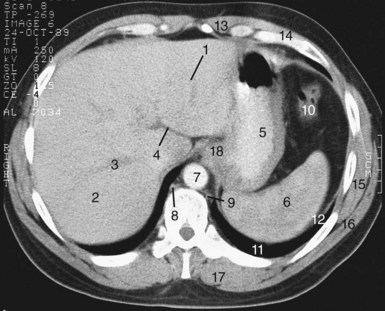

Gastric cardia radiology. Diagnostic centers of america dca is a leading diagnostic imaging facility offering a full array of imaging services in palm beach county florida. We have five state of the art radiology imaging centers in boca raton boynton beach delray beach and wellington florida. The gastric cardia is characterized on barium stud ies by three or four stellate folds that radiate to a central point at the gastro esophageal junction also known as the cardiac rosette fig 2 12. Variations and benign influences may closely resemble the more dangerous lesion.

Cain jc jordan gl jr comfort mw gray hk. J am med assoc. The gas tric fundus is dened as the portion of the stomach craniad to the gastric car dia. Commonly accompanying this are abnormally dilated short gastric veins which pass from the splenic vein to encircle the gastric fundus and form gastric fundal varices.